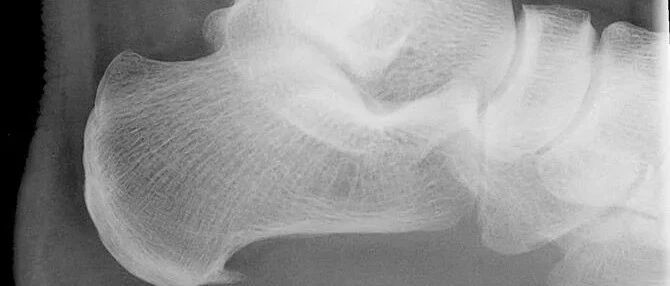

ED本身是一种与年龄密切相关的疾病。随着年龄的增长,雄激素水平的不断下降,心血管疾病发生率也在升高,种种因素共同促进这ED的发生。70岁以上男性的发病率可达70%~100%。

随着年龄增长,ED发病率增加。

图片来源:参考文献[6]